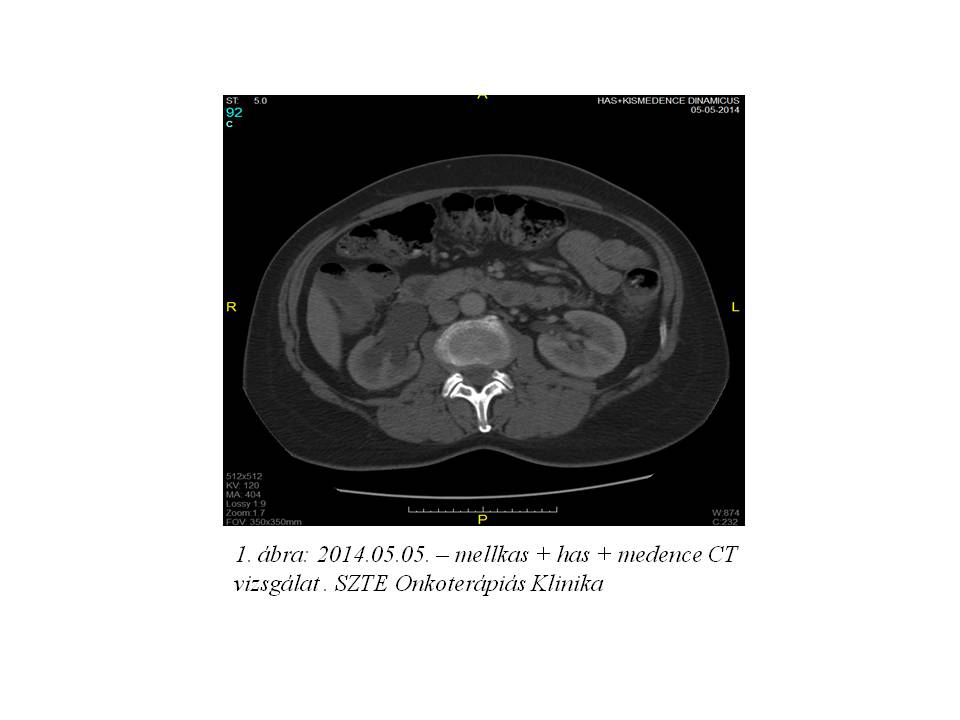

2014. márciusban a beteg rendellenes hüvelyi vérzés miatt jelentkezett nőgyógyászati kontrollon. Fizikális vizsgálattal egyértelműen recidíva nem igazolódott. Has + kismedencei CT vizsgálat történt, mely multiplex hepaticus metastasisokat, valamint jobb oldali pyelectasia mellett a hólyag és a rectum közötti régióban kismedencei recidíva radiológiai képét, és a jobb tüdőbázison is bizonytalan gócot írt le. (1. ábra, 2. ábra, 3. ábra, 4. ábra).